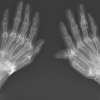

손 안 ‘금침’ 빽빽…한국 50대女 엑스레이, 국제학술지 실려

2017-11-17 나우뉴스 -